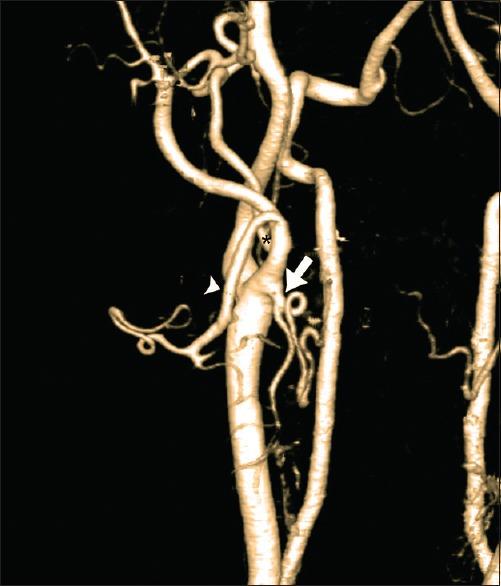

We studied levels of carotid bifurcation compared relatively with the level of the vertebral body and ipsilateral angle of the mandible and its branching pattern using computed tomographic angiogram (CTA) carotid with multiplanar reconstruction and three-dimensional imaging in 100 CTA studies.

我们在100例计算机断层血管造影(CTA)研究中,使用多平面重建和三维成像的CTA颈动脉,将颈动脉分叉的位置与椎体水平和同侧下颌角进行相对比较,并研究其分支模式。

大多数颈动脉分叉位于C3 - C4椎体水平,12%被认为是高位分叉。83.5%的颈动脉分叉位于下颌角以下。67.7%的样本中,甲状腺上动脉、面动脉和舌动脉分别起自颈外动脉的不同分支。29.2%的样本中,面动脉与舌动脉共干发出,比以往尸体研究更为常见。2%的样本中,舌动脉与甲状腺上动脉共干发出,而枕动脉的分支模式变异较大。

结论

CTA是对接受颈动脉内膜切除术及其他颈动脉手术患者进行颈动脉系统术前评估的有效且可靠的方法。我们的研究中发现高位颈动脉分叉的比例较高,与其他亚洲尸体研究结果一致。我们推测亚洲人的颈动脉分叉位置往往比白种人略高。